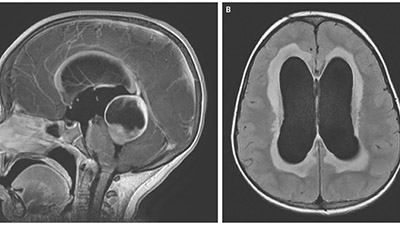

جمع شدن آب در سر